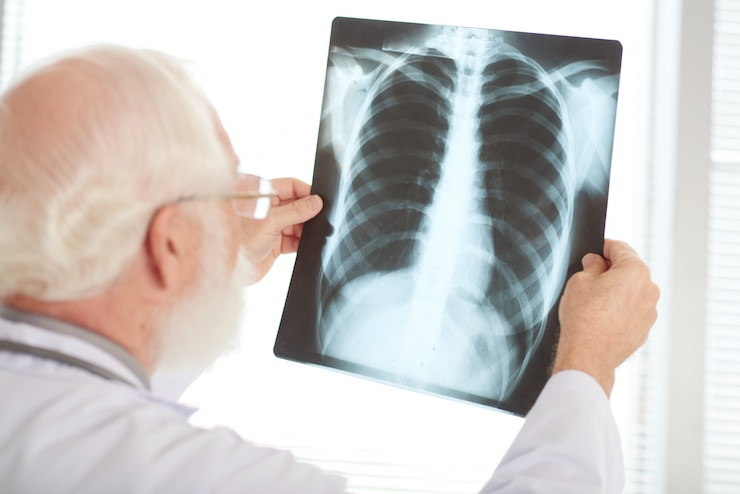

1) 흉부 X-ray, CT 촬영 요청

기침, 흉통, 피 섞인 가래 등이 2주 이상 지속된다면 흉부 X-ray와 CT 검사를 바로 요청하세요.

2) 폐암 고위험군은 정기검진 필수

50세 이상 + 30갑년 이상의 흡연력 보유자는 1~2년 간격으로 저선량 CT 촬영이 권장됩니다.